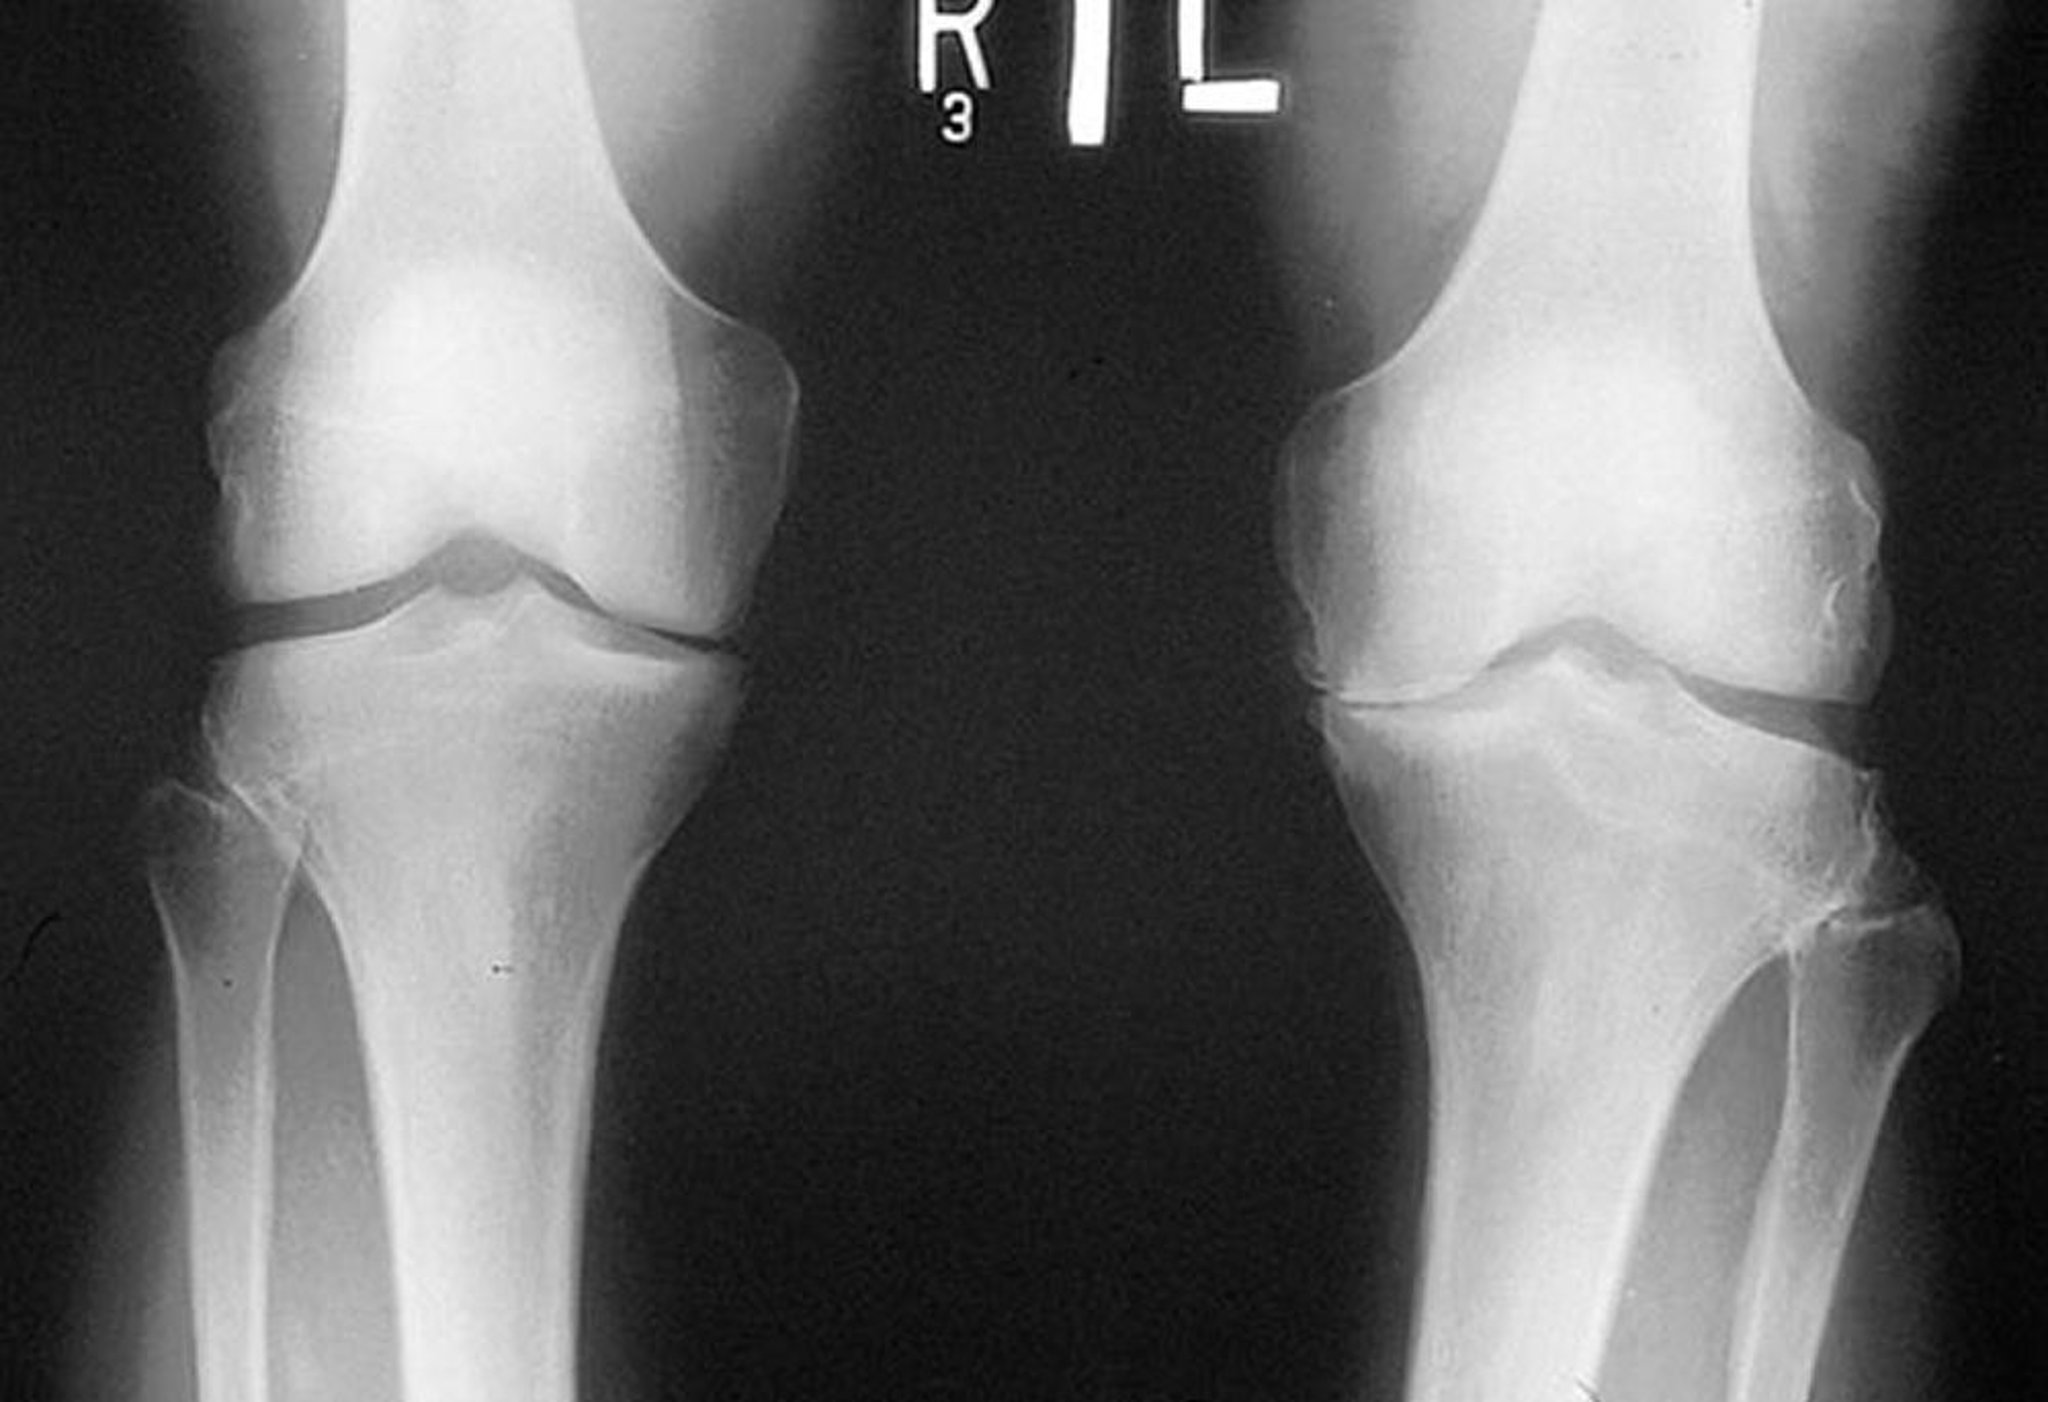

Рентгенологическое исследование коленного сустава при остеоартрозе

На рентгенограмме, сделанной в положении стоя, показано сужение большеберцово-бедренной суставной щели в медиальных отделах обоих колен, особенно слева. Определяются краевые костные разрастания. Истирание левой медиальной части плато большеберцовой кости.

By permission of the publisher. From Myers S: Atlas of Rheumatology. Edited by G Hunder. Philadelphia, Current Medicine, 2005.